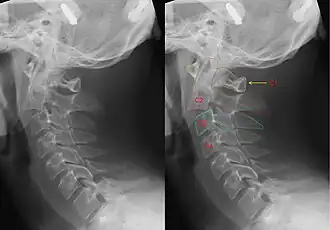

Рентгенограмма шейного отдела пациента с переломом палача